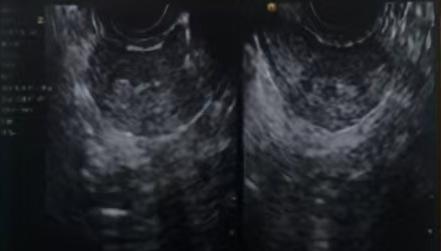

2024年10月21日本院超声提示:子宫大小37mm*31mm*40mm,子宫全层厚3.5mm,子宫内膜连续性中断,考虑宫腔粘连可能。

苏州大学附属第一医院超声图示